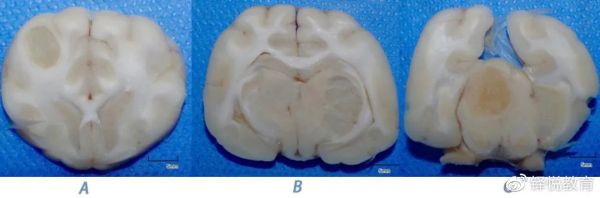

主人未同意活检,选择安乐死。经允许后进行安乐死后尸体检查。

尸检取下脑组织后,福尔马林固定 24 小时后进行大体切片观察,可见边缘清晰的光亮略透明病灶侵袭右侧顶叶、左外侧丘脑和右侧中脑的灰白质交界处,与 MRI 表现一致。三个部位的肿物均进行了组织病理学检查,三个肿物的病理结果是一致的。

图片图片

图 5 右侧顶叶薛氏上回皮质下(A)、左外侧丘脑(B)和右侧中脑(C)的三处肿物的大体解剖。